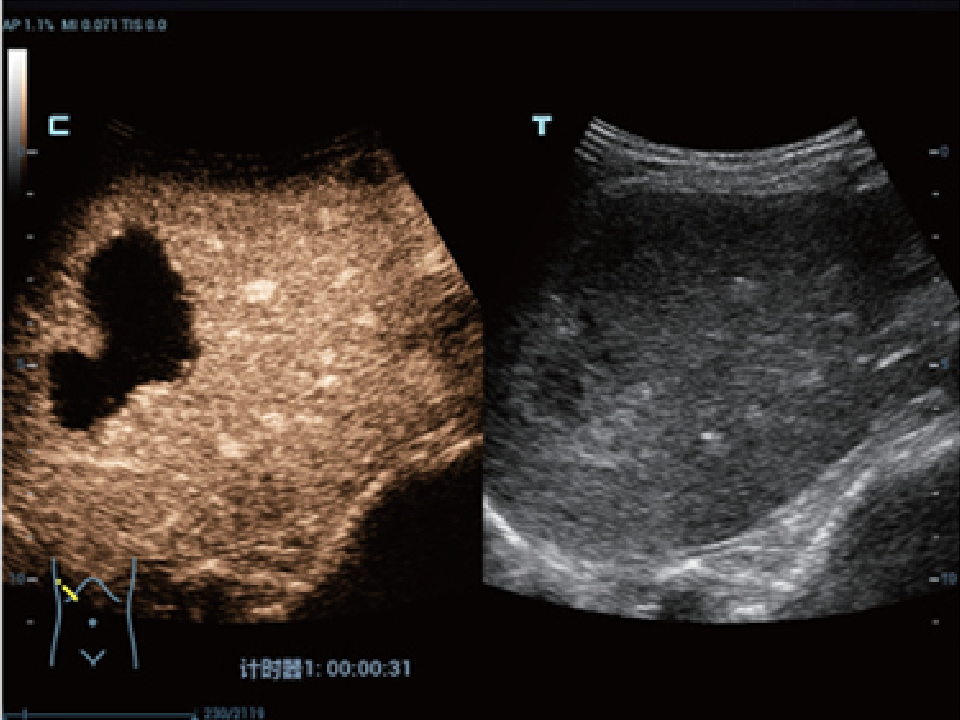

eXceptional Intelligence

Intelligence throughout entire workflow

Intelligence integrated in professional diagnostic tools for whole examination procedures,DC-80 with X-Insight provides exceptional intelligence integrated in professional diagnostic tools across wide applications and throughout whole examination procedures, from regular screening to further diagnosis and clinical follow up.